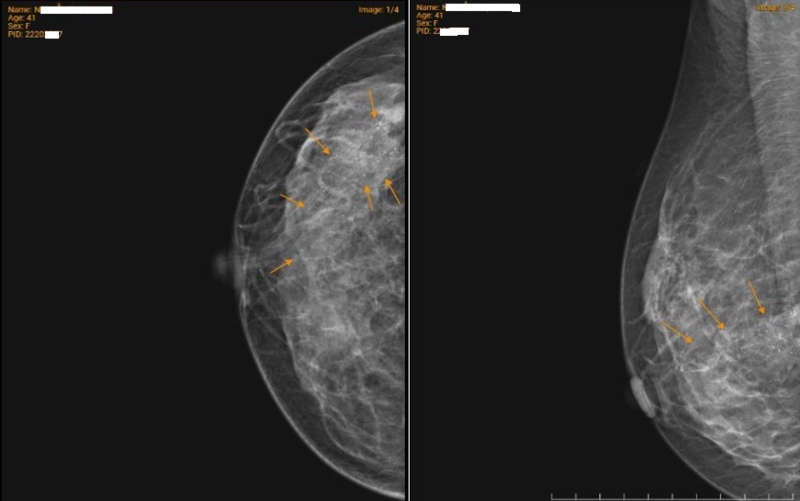

Kết quả siêu âm tuyến vú phát hiện đám giảm âm kèm giãn ống tuyến vú phải, được phân loại BIRADS 4 – mức độ nghi ngờ tổn thương ác tính. Chụp X-quang tuyến vú ghi nhận nốt vôi hóa tập trung thành đám tại vú phải, phân loại BIRADS 4B.

Chụp X-quang tuyến vú ghi nhận nốt vôi hóa tập trung thành đám tại vú phải